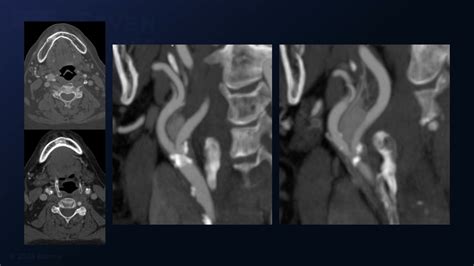

CT Angiography (CTA) Provides detailed views of the tumor's size and its relationship to major arteries.

Diagnosing a Carotid Body Tumor requires a combination of physical examination and advanced imaging studies. When a physician suspects such a growth, they typically use specific diagnostic tools to differentiate it from enlarged lymph nodes or other neck masses. The “Lyre sign,” seen on imaging, is a classic finding where the internal and external carotid arteries are splayed apart by the tumor mass.